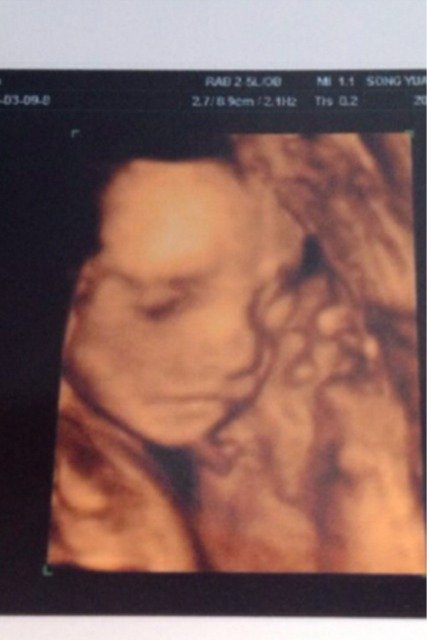

这样看我宝宝是不是大鼻子、大嘴巴,大眼睛呢?眼毛是不是很黑 这样看我宝宝是不是大鼻子、大嘴巴,大眼睛呢?眼毛是不是很黑 点击展开 含蓄, 2015-04-14 13:58 为您推荐: 其他回答 刚出生的宝宝没眉毛 胖团妈咪 2015-04-14 16:21 很难看出来 妈妈爱大宁宝宝。 2015-04-14 15:37 可爱*^o^* 小臭子麻麻 2015-04-14 14:51 看起来很可爱 151*****093_O0ce 2015-04-14 14:48 小宝贝一点会是很美丽的! 小小Vanessa爱喝奶 2015-04-14 14:25 加载更多 相关问题 有没有思维照片照的宝宝大鼻子大嘴巴,生出来后不一样的? 为什么宝宝三维照大鼻子大嘴巴,不像我们啊? 今天老婆照4维了…宝宝大鼻子大嘴巴像老公!谁看的懂是男宝宝女宝宝呀